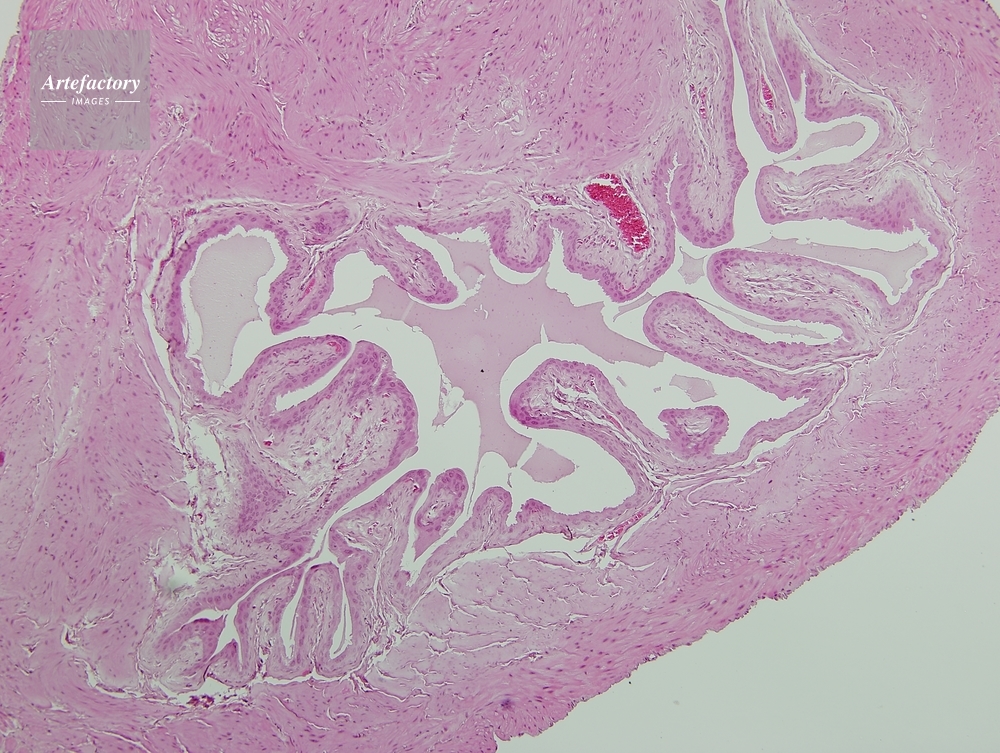

| 作品タイトル | マウス,膀胱 | モデルリリース | なし | |

| 作家 | OLYMPUS CORPORATION Technolab | プロパティリリース | なし | |